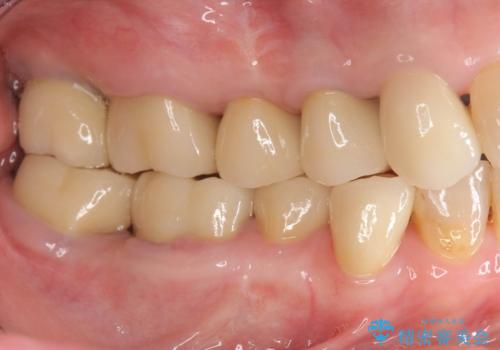

期間は約2年ほどかかりましたが、審美的な仕上がりとともに清掃のしやすさも非常に満足いただくことができました。